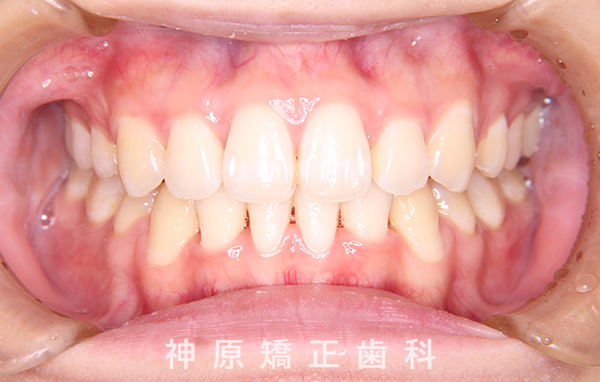

治療終了

治療前と治療後

今回の矯正治療を行う上で、矯正精密検査の結果口元の突出感の改善と下の歯のガタガタを改善するために小臼歯を抜歯する必要があると判断いたしました。